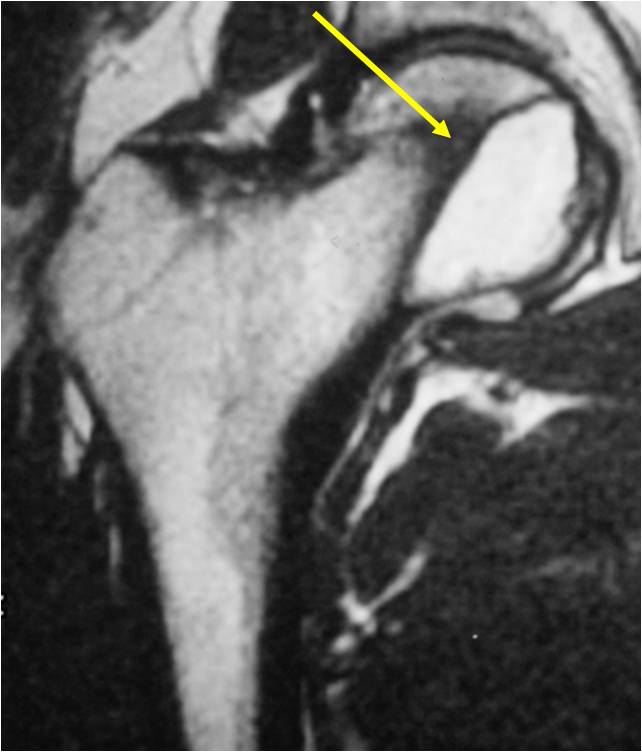

Sites:

- Epiphyses of long bones

- Most commonly proximal femur, proximal humerus, distal femur, proximal tibia

Radiographic Presentation

- Usually osteolytic, expansile lesion

- May be focally calcified

- Often a sharp interface between tumor and surrounding bone

- Sclerotic rim is uncommon

- Overlying cortex is usually thin, but intact